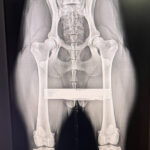

Vi röntgar enligt SKK:s riktlinjer med hög noggrannhet för en sund avel och friska hundar.

Och ja – vi röntgar även katter! 🐱 På sista bilden ser ni en HD-bild på en Maine Coon.